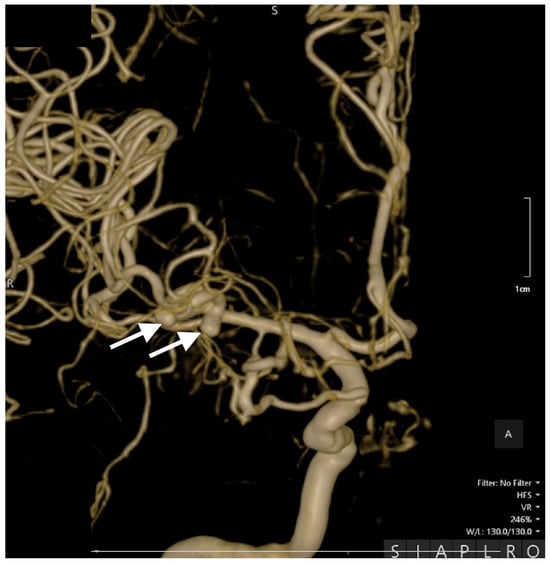

Postoperative cerebral CT scans showed a right frontotemporal hypodensity suggestive of sequelae of the ischemic stroke, correlating with her left-sided motor deficit (Figure 4).

Figure 4. Postoperative CT scan. All three sections, transversal (left image), coronal (middle image), and sagittal (right image), show clip placement (white arrows) and sequelae from the ischemic stroke. The yellow arrows indicate areas of hypodensity corresponding to ischemic stroke sequelae in the right frontotemporal region.